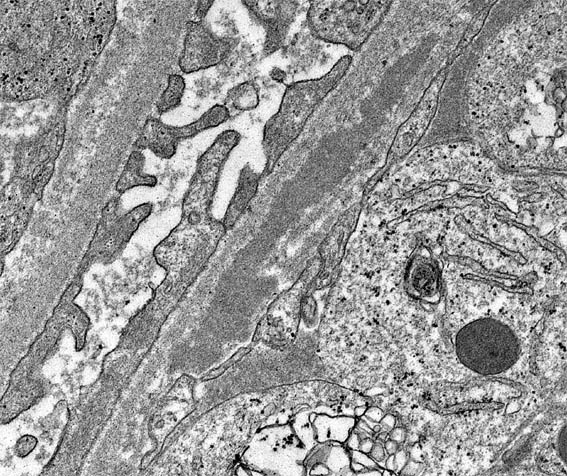

Figura 6. ME, aumento original: X6.000.